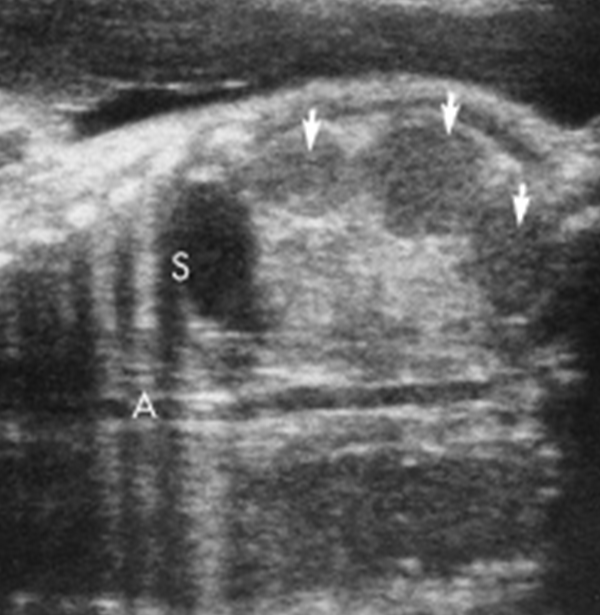

multicystic kidney disease